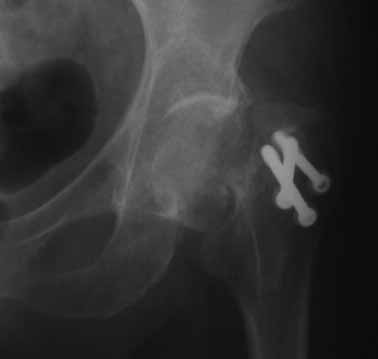

На консультации вот такие снимки. Больная 72 года. упала в быту 26 декабря 2010г.

Оперирована 30 декабря 2010г. в одном из стационаров края. Назначили дополнительное обследование, а пока хотелось-бы услышать мнение по-поводу возможностей сохранения головки. Больная из льготного контингента, т.е. современные констукции и эндопротез маловероятны.